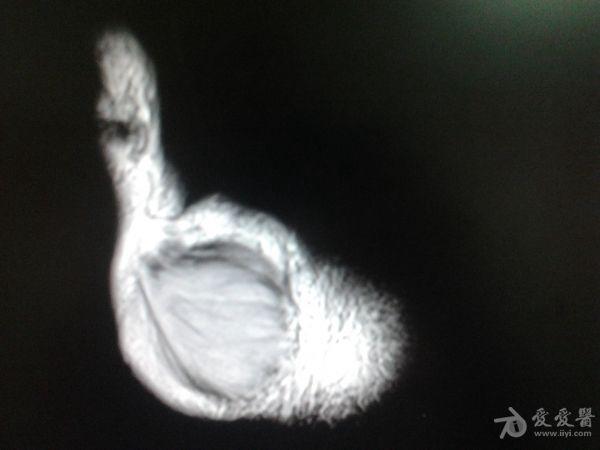

右第一掌骨、大多角骨肿瘤

男性患者,81岁,右手肿痛3个多月。无任何其它症状。体查:右手第一掌骨部肿胀明显,第一指活动受限,余四指活动可,腕关节活动小部分受限,活动时会痛。影像学检查如下。活检示:弥漫性大B细胞淋巴瘤。大家看看需不需要截肢?现在有人主张手术;有人主张不手术,直接化疗。大家有什么看法?